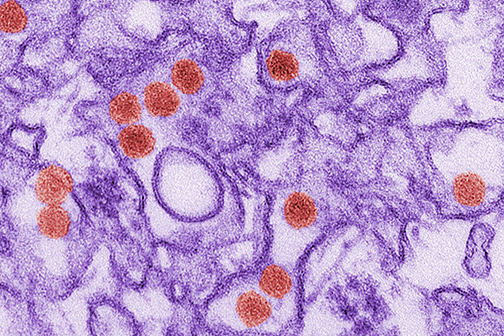

LSU Health Hosts Special Monkeypox Education Event Friday

LSU Health New Orleans School of Medicine will host a special Grand Rounds with the latest and detailed information about monkeypox, declared a Global Public Health Emergency. Monkeypox: What we know…. What we need to know is scheduled for Friday, August 5, 2022, from 12:00 noon - 1:00 p.m. on LSU Health New Orleans’ downtown campus in the first-floor Lecture Room A of the Medical Education Building, 1901 Perdido Street. More

LSU Health New Orleans Precision Medicine Lab Finds New Omicron Subvariants

LSU Health New Orleans’ Precision Medicine Lab has found two new SARS-CoV-2 variants in Louisiana. BE.1 and BF.1 are subvariants of the Omicron Variant of Concern that has driven the latest surge. The Lab identified three cases of BE.1 and one case of BF.1 in tests performed at the end of June. More

LSU Health New Orleans Precision Medicine Lab Finds Omicron Variant

Among the 567 new COVID-19 cases reported today in Louisiana are two confirmed cases of the Omicron variant from the New Orleans area found by the LSU Health New Orleans’ Precision Medicine Laboratory. Directed by Lucio Miele, MD, PhD, Professor and Chair of Genetics at LSU Health New Orleans School of Medicine, along with Dr. Gordon Love, Professor and Chair of Pathology, the lab sequences samples from positive tests to learn what strains of the virus that causes COVID-19 are infecting patients here. More

1st Delta Variant Case Confirmed in Area

The Precision Medicine Lab at LSU Health New Orleans School of Medicine has identified the first Delta variant COVID case in Region 1 of Louisiana, which includes the New Orleans metropolitan area. More

LSU Health New Orleans Awarded $2.38M to Sequence COVID-19 Virus Variants

LSU Health New Orleans has been awarded $2.38 million in funding to lead partnerships to sequence SARS-CoV-2 variants. The funding is from a contract with the Louisiana Department of Health (LDH)) and a National Institute of General Medical Sciences supplement to the LACaTS (Louisiana Clinical & Translational Science Center) grant. More

LSU Health New Orleans Study Reports Compound Blocks SARS-CoV-2 and Protects Lung Cells

Research conducted at LSU Health New Orleans Neuroscience Center of Excellence reports that Elovanoids, bioactive chemical messengers made from omega-3 very-long-chain polyunsaturated fatty acids discovered by the Bazan lab in 2017, may block the virus that causes COVID-19 from entering cells and protect the air cells (alveoli) of the lung. More